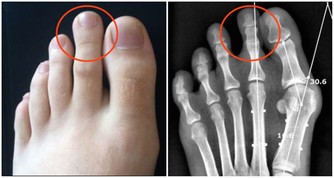

4、全身疼痛——缺乏維生素D 曬太陽不足、或維生素D缺乏的人,就容易引起慢性疼痛,加上維生素D是人體無法自行合成的營養素,補充更為重要。維生素D也是促進骨骼生長、牙齒健全的重要物質。